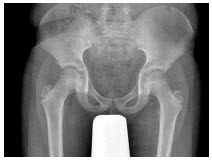

27、单项选择题

男,38岁,右髋关节疼痛不适1年余,跛行,骨盆正位片如图所示,最可能的诊断是()

168、单项选择题

男,根据其正常骨盆影像图像,判断其最可能的年龄()